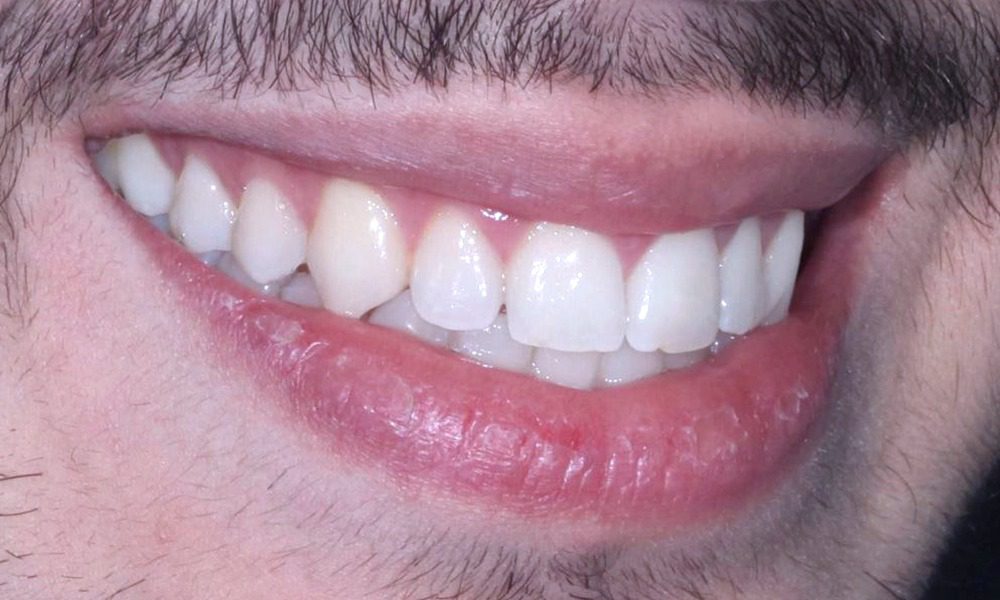

DİJİTAL GÜLÜŞ TASARIMI-DSD (DIGITAL SMILE DESIGN)

Ağız ortamına süren diş, sürdüğü anda en mükemmel haldedir. Süreçte asite,travmaya maruz kalmaya başlar, aşınmalar, mine çatlakları, çürükler, renklenmeler görülür. Yüzey artık parlaklığını ve bütünlüğünü kaybeder. Bu değişim önlenemeyen bir yaşlanma sürecidir. Bu süreci başa almak mümkün değil, ama durdurmak bu tedavi protokolü ile mümkündür. Böylelikle, ilk zamanlardaki bütünlük, parlaklık, renk, estetik sağlanabildiği gibi, koruyucu bir yaklaşımla sürecin olumsuz olabilecek etkilerinin de önüne geçilmiş olur...